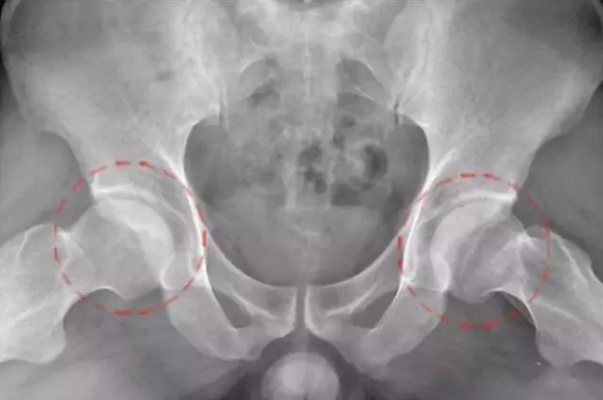

股骨头坏死又称股骨头无菌性坏死,或股骨头缺血性坏死,是骨坏死的一种。股骨头局部血运不良,引发股骨头血液循环障碍,从而使得股骨头进一步缺血、坏死、骨小梁断裂、股骨头塌陷的一种病变。股骨头坏死的原因西医大致概括为外伤、激素使用过量、酗酒、先天性发育、职业病以及其他疾病后期并发症等,现代医学目前尚无有效的治疗药物

跛行:早期由于疼痛导致间歇性跛行,中晚期股骨头塌陷导致,儿童更为明显。